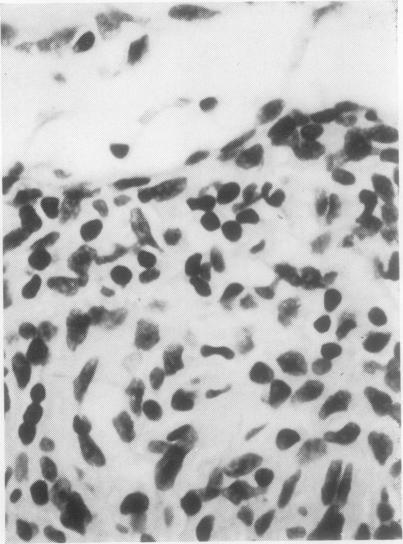

The histopathological appearances of the thymus, lymph nodes, spleen, and gut-associated lymphoid tissue (tonsil, Peyer's patches, and appendix) in cases of the combined immunity-deficiency syndrome are presented. The appearance of tissues remaining after foetal thymic transplants and the effects of such transplants on the morphology of lymph nodes are also discussed. Although thymic appearances are remarkably constant the picture in the lymph nodes and spleen may vary considerably. The tonsils, Peyer's patches, and appendix appear to constitute one lymphoid organ in man, at least with regard to the developmental arrest that may occur in this syndrome.

本文呈现了联合免疫缺陷综合征病例中胸腺、淋巴结、脾脏及肠道相关淋巴组织(扁桃体、派伊尔结和阑尾)的组织病理学表现。还讨论了胎儿胸腺移植后剩余组织的外观以及此类移植对淋巴结形态的影响。尽管胸腺的表现非常一致,但淋巴结和脾脏的情况可能有很大差异。扁桃体、派伊尔结和阑尾在人类中似乎构成一个淋巴器官,至少就该综合征可能出现的发育停滞而言是这样。